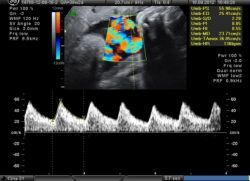

В целом, состояние пуповины и ее возможные патологии обнаружить во время беременности достаточно затруднительно. Как правило, проводят ультразвуковую диагностику, которая позволяет выявить обвитие пупочного канатика вокруг шеи, конечностей и туловища плода, а также ее предлежание. При помощи фонокардиографии и аускультации могут быть выявлены не только пороки сердца, но и шум сосудов пуповины, который появляется в связи с обвитием туловища или шеи ребенка. Также врачи могут использовать метод цветового картирования, при котором хорошо просматриваются все пуповинные артерии, вена и допплерометрия, позволяющая оценить, в том числе, и состояние маточно-плацентарного кровотока. При влагалищном исследовании выявляется выпадение петель пуповины. После рождения последа осматривают плаценту и пупочный канатик и при необходимости отправляют материал на гистологическое исследование.

Наиболее достоверные сведения о состоянии пуповины и ее сосудов можно получить при ультразвуковом исследовании с цветным допплеровским картированием.

Поперечный «срез» пуповины показывает наличие более крупного сосуда – вены, и меньшего по диаметру – артерии. Количество сосудов оценивают по продольному изображению.

- Цветовое допплеровское картирование (ЦДК). В ходе данной процедуры осуществляется ультразвуковое исследование с дополнительным анализом кровообращения с применением допплеровского эффекта. При проведении манипуляции получается цветное изображение процесса циркуляции крови в исследуемой области, наложенное на черно-белую картинку, полученную по результатам УЗИ. Этот метод является наиболее достоверным и эффективным. Он позволяет определить обвитие пуповины вокруг шеи, конечностей и тела ребенка. Кроме того, с помощью такой методики выявляется предлежание детского места. Сведения о числе сосудов можно получить примерно на 12-недельном сроке гестации, когда беременная пациентка направляется на первое скрининговое исследование.